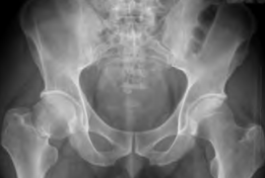

为追求更安全有效的青壮年股骨颈骨折治疗方式,我院创伤骨科成功实施了更微创、更符合生物力学特点的内固定方式—股骨颈动力防旋系统,其创伤小、恢复快、并发症少,在国内外的研究中已取得显著疗效。2021年7月我科收治了一名34岁右侧股骨颈骨折的男性病人,术前影像学检查如图2所示。

图2术前X线和CT检查